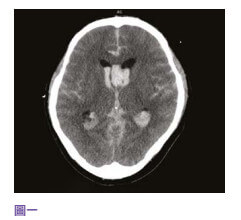

中风当时39岁的李先生三年前,39岁的李先生是位地盘工人,已婚育有一名幼子,为家庭经济支柱。 他身体一向健康,经常运动而且不烟不酒。 某日在工地里突然急剧头痛,继而晕倒在地。 工友立即召唤救护车将他送往附近的公立医院,送院时李先生还是半清醒。 电脑扫描显示他脑部有蜘蛛网膜下腔出血性中风(见图四),从造影可以看到一个约一至二毫米的动脉瘤在李先生大脑的前交通动脉血管之上(见图五)。 不幸的是,在医院观察的第二天早上,李先生突然深度昏迷,紧急电脑扫描显示动脉瘤第二次爆破,而且造成脑部严重积血、颅内压飙升,专科医生需要做紧急开颅手术去清除脑内血块,并将脑室引流以减低脑积水和颅内压(见图六),同时用钛金属夹将爆破的动脉瘤夹闭(见图七),防止它再次爆破。